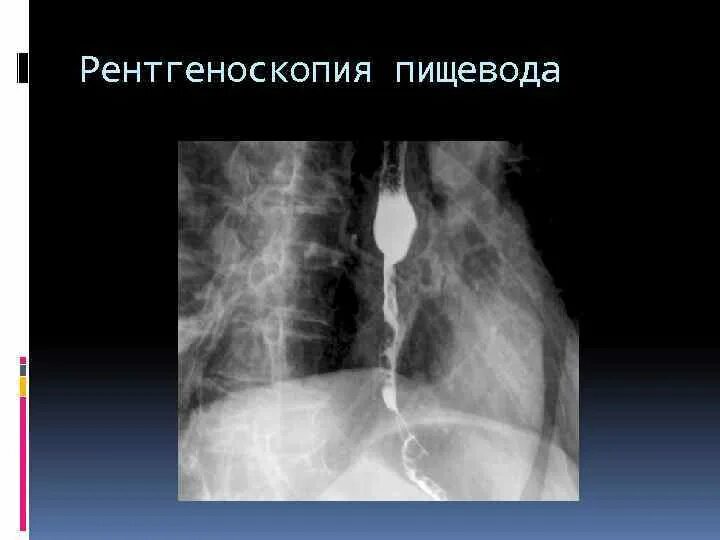

Рентгеноскопия пищевода и желудка с барием

Полипозиционная рентгеноскопия пищевода. рентгенография пищевода с барием. рентгенологическое исследование пищевода с бариевой взвесью.

Рентгеноскопия пищевода с барием. рентген с барием пищевода и желудка.